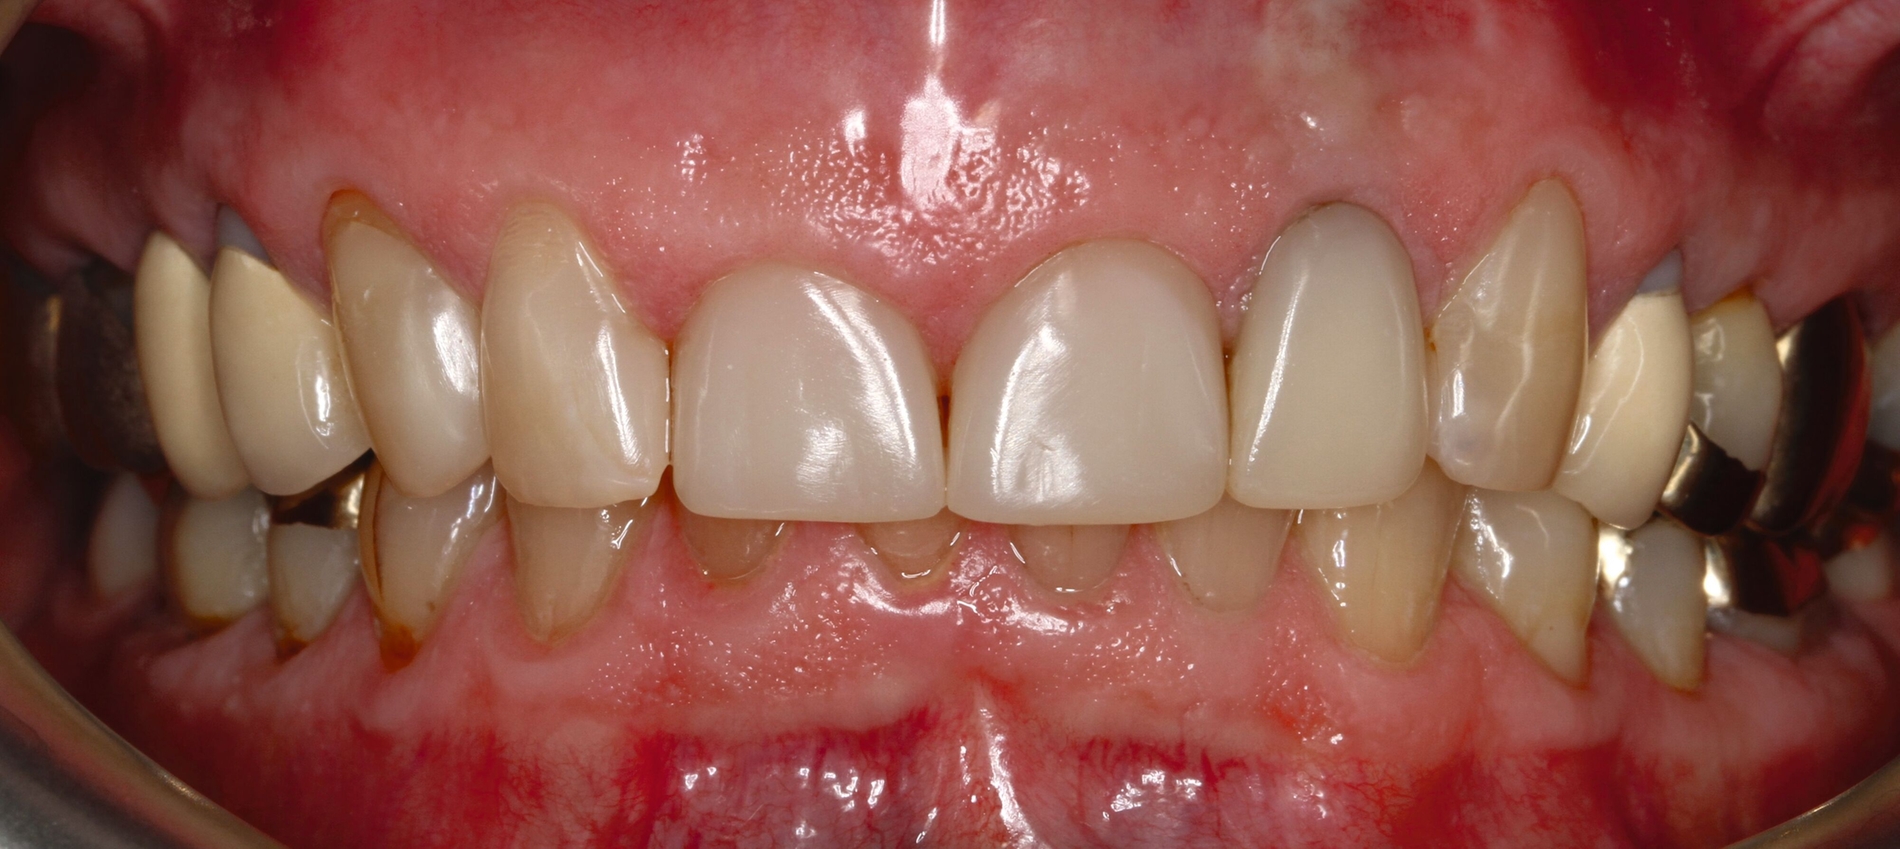

Die dentale Ausgangssituation zeigte im Seitenzahnbereich ein suffizient konservierend und prothetisch versorgtes Gebiss der zweiten Dentition sowie im Frontzahnbereich nicht kariogene Zahnhartsubstanzverluste und eine defekte Krone mit Sekundärkaries (Abbildungen 1 und 2).

Zur Verbesserung der Ästhetik und des Wohlbefindens des Patienten standen die Harmonisierung der Lachlinie und des Frontzahnbogens sowie Farb- und Formkorrekturen der Oberkieferfrontzähne im Fokus. An den Zähnen 11 und 21 waren Zahnhartsubstanzverluste durch Erosion und Attrition zu erkennen. Zahn 23 hatte ebenfalls einen erosiven Defekt, Zahn 13 eine farblich abweichende Kompositrestauration und die Zähne 14 und 24 wiesen keilförmige Defekte zervikal der Kronenränder auf, die einen suffizienten Randschluss haben (Abbildung 1a).

Die Zähne 11, 21 und 32–42 wiesen aufgrund des Zahnverschleißes stark verkürzte klinische Kronen auf. Durch diese Zahnhartsubstanzverluste sind die genannten Zähne über die Zeit elongiert – gut erkennbar an dem in Richtung Okklusionsebene verschobenen Verlauf des Gingivalsaums –, wodurch sich ein frontaler Tiefbiss und in Protrusion eine verzahnte Frontzahnführung im Schlüssel-Schloss-Prinzip mit veränderter Rot-Weiß-Ästhetik adaptiert haben. Daraus resultiert ein verringertes Platzangebot in statischer und in dynamischer Okklusion (Abbildungen 1b und 1d).